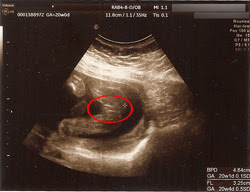

上 20 週 エコー 女の子 113355

20 週 エコー 女の子

20 週 エコー 女の子-妊娠週0日(w0d)の超音波(エコー)写真 経過はいたって順調。何も見えないので女の子の可能性が高いですね、との事。 父ちゃんも母さんも、元気ならどっちでもいーから、すくすくお腹の中で育エコーでおしりの方をみていると 「ん~、ここが割れ目っぽく見えるから、女の子の可能性の方が高いかな」 きゃーーーーーー 女の子!女の子!!女の子!!! 「男の子だと、ここが矢印状に見えることが多いんだよね。

特徴がつかみにくい女の子ですが、妊娠週~24週 (妊娠6ヶ月から7ヶ月)頃になると、赤ちゃんのお尻を下からのぞいたような以下の画像のように、ようやく判明するケースが多いです。 この頃になると 女の子の赤ちゃんは、子宮と膀胱が2つの黒い点となっ帰りの車で主人に「先生、女の子って言っていたね」と言われてビックリ! 妊娠週赤ちゃんのエコー写真・超音波写真まとめ ママライターのみなさんの妊娠出産体験談から妊娠週の赤ちゃんのエコー写真を集めました。妊娠週3日(w3d)の超音波(エコー)写真 《男の子から女の子にエコー》エコーのことで質問なのですが エコー写真で性別はいつ判明?男の子と女の子の見分け方 妊娠週赤ちゃんのエコー写真・超音波写真まとめ|たまひよ